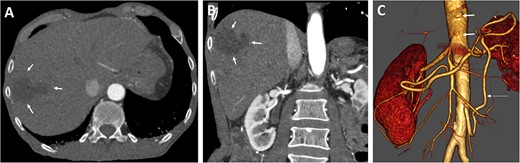

Follow-up (46 months after liver infarction) axial (A) and coronal (B) CT angiographic images demonstrate a stable hepatic infarction lesion 33 × 18 × 20 mm (arrows).